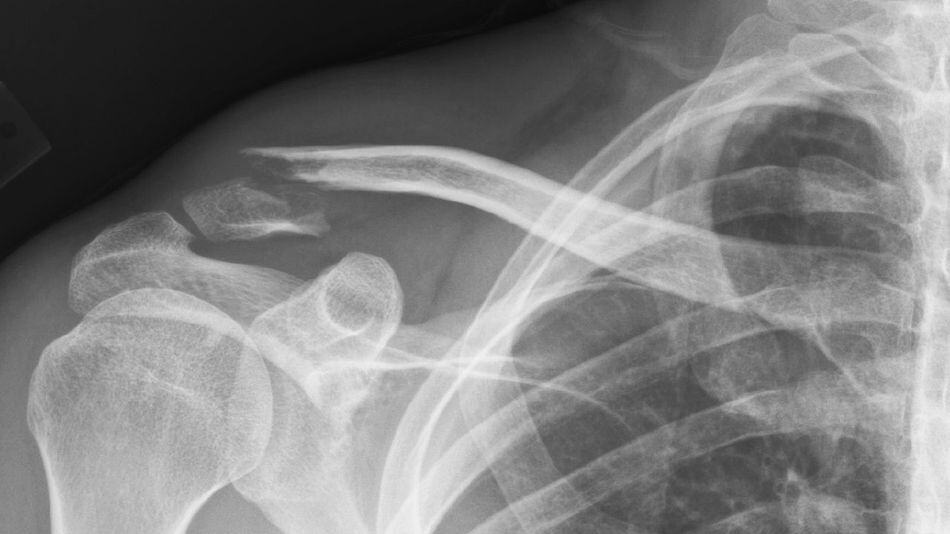

The research group tested hundreds of combinations of plastics and biomaterials, to identify a blend that was biocompatible, robust, lightweight, and able to support bone stem cell proliferation. Results from in vitro and animal in vivo testing unveiled the optimal formulation of the chitosan + PLA + PVA blended 3-D hydrogel scaffold. The material resulted in a tough yet highly porous scaffold material. This may make it an ideal scaffold for a broken bone – a placeholder structure that can be replaced with real bone tissue as the body heals.

Oreffo’s team tested the polymer in mice that had parts of their femur bones removed. The resulting hole was a size “that won’t heal normally,” Oreffo said. “We put these scaffolds into that [gap] and seen their repair over four to eight weeks.” Further, when the scaffold was seeded with human bone stem cells, the bone healed faster, but even without the stem cells, the mice’s bones began to fill in along the scaffolding structure.

In humans, the structure should serve to repair bone breaks that are too severe to heal on their own. “If you’ve had a car accident where you’ve had significant bone breaks … ideally, you want your own stem cells in there,” Oreffo said. “This is a real opportunity: A scaffold that can be colonized with the patient’s own stem cells.”